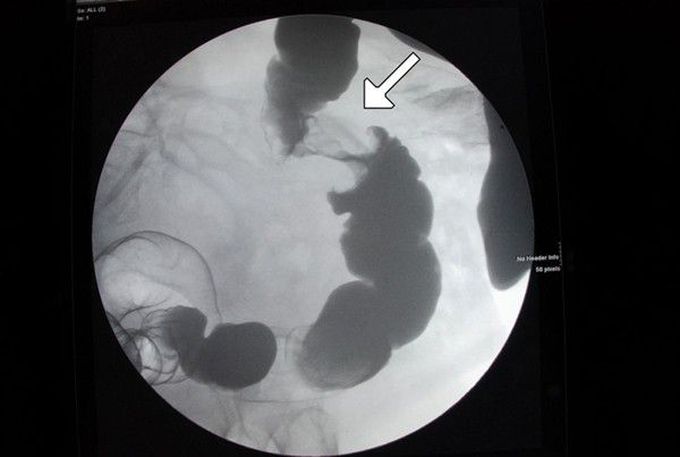

Apple Core Lesion Of The Colon Shown On Barium Enema Arrow Download Scientific Diagram